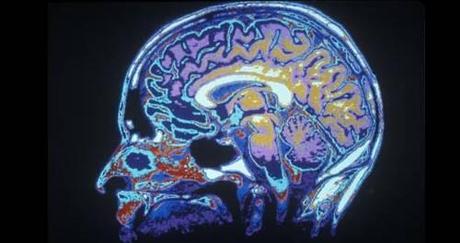

Vemos muchas historias ilustradas con imágenes cerebrales funcionales (fMRI). ¿Qué miden estas imágenes?

La sigla fMRI proviene de functional magnetic resonance imaging o imagen por resonancia magnética funcional y, para hacerla corta, mide dónde se acumula sangre rica en oxígeno en el cerebro, mientras que el subsecuente análisis estadístico intenta decirnos cuán fielmente estos cambios en el flujo sanguíneo están asociados con una tarea mental específica mientras es testeada. Como las áreas más activas necesitan más oxígeno, medir la sangre oxigenada es una manera de inferir dónde se está realizando más “trabajo”.

¿Cuáles son las limitaciones de los estudios de fMRI?

Primero, el flujo sanguíneo no es una gran guía para ver la actividad cerebral – tiende a seguir temporalmente a la actividad neuronal de manera desigual. Segundo, la fMRI no tiene la misma sensibilidad a través de todo el cerebro, es decir, algunas áreas pueden parecer menos activas cuando no lo son. Pero la limitación más importante viene de las dificultades al usar las estadísticas para analizar la enorme cantidad de datos que esta técnica produce. Diferentes técnicas estadísticas pueden producir diferentes resultados. Todas las imágenes del cerebro necesitan más que un poco de interpretación y, a veces, una pizca de sal.